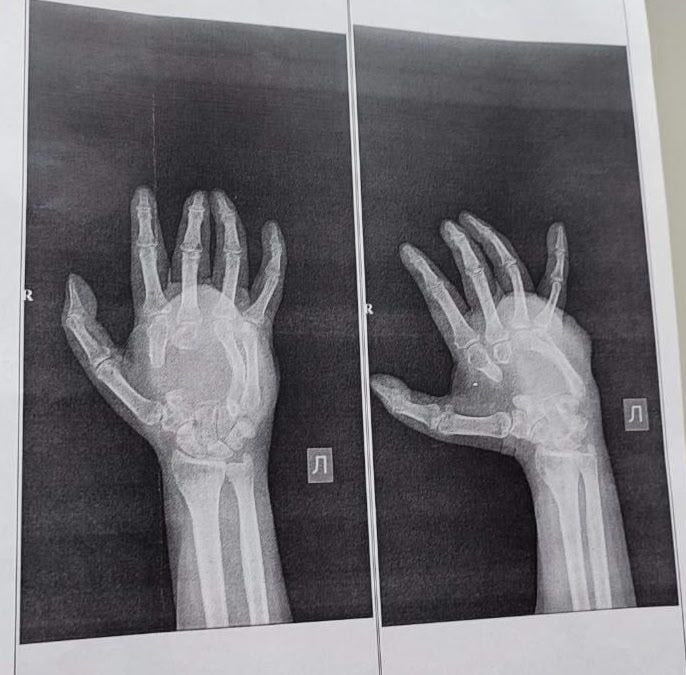

Врачи Кузбасского клинического центра охраны здоровья шахтеров им. святой Варвары в Ленинске-Кузнецком работают над восстановлением кисти бойца СВО. В результате полученного ранения в зоне спецоперации у военнослужащего были повреждены пястные кости, сухожилия и нервы.

Специалисты уже провели первый этап восстановления — костную пластику. Для устранения серьезных дефектов медики использовали собственные ткани пациента из тазовой кости, сообщил министр здравоохранения Кузбасса.

Сейчас врачи ожидают приживления трансплантатов. Следующий этап — пластика сухожилий и восстановление нервов. Только после этого кисть военнослужащего снова станет подвижной и обретет чувствительность.